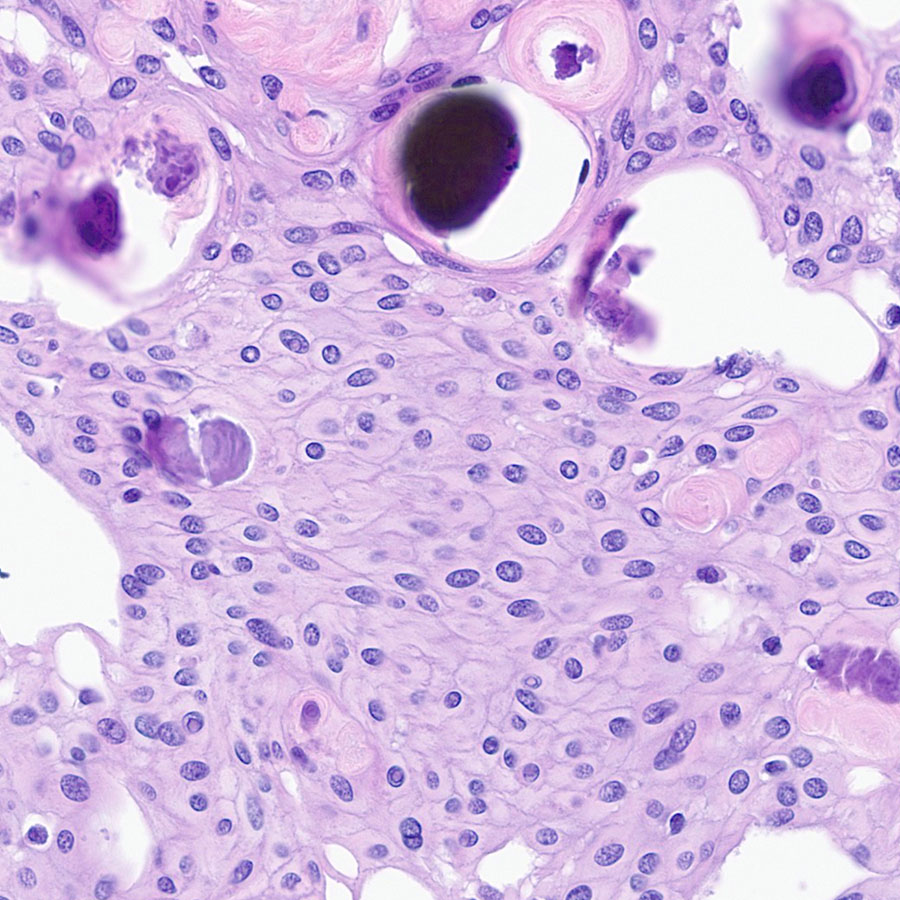

@CraigHorbinski

Craig Horbinski

12 days

Fairly prominent cell borders in a meningioma, rather unusual...

0

10

53